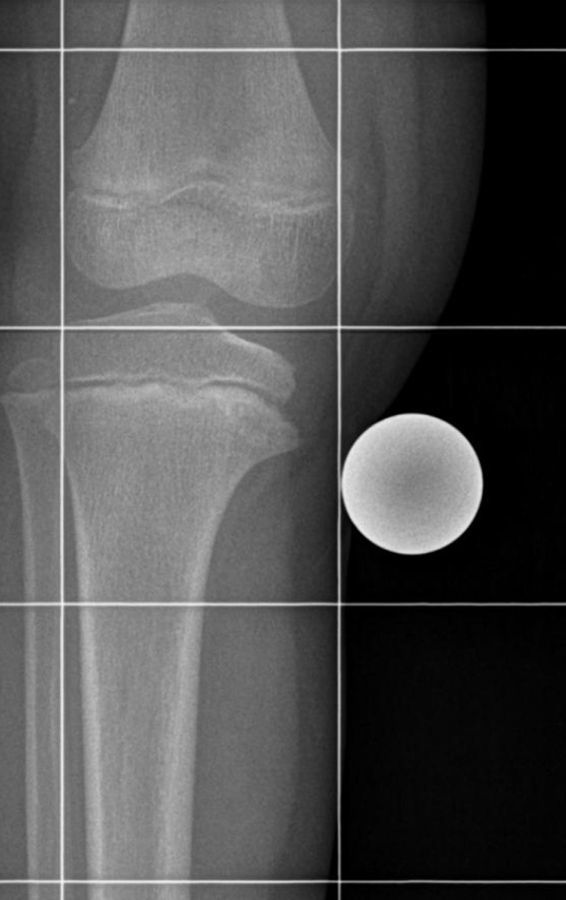

Das Patellaspitzensyndrom (M. Sinding-Larsen-Johansson) ist quasi der weibliche M. Osgood-Schlatter mit einer Osteonekrose der Patellaspitze. Das Patellaspitzensyndrom (M. Sinding-Larsen-Johansson) ist quasi der weibliche M. Osgood-Schlatter mit einer Osteonekrose der Patellaspitze. © wikimedia/nomen 49